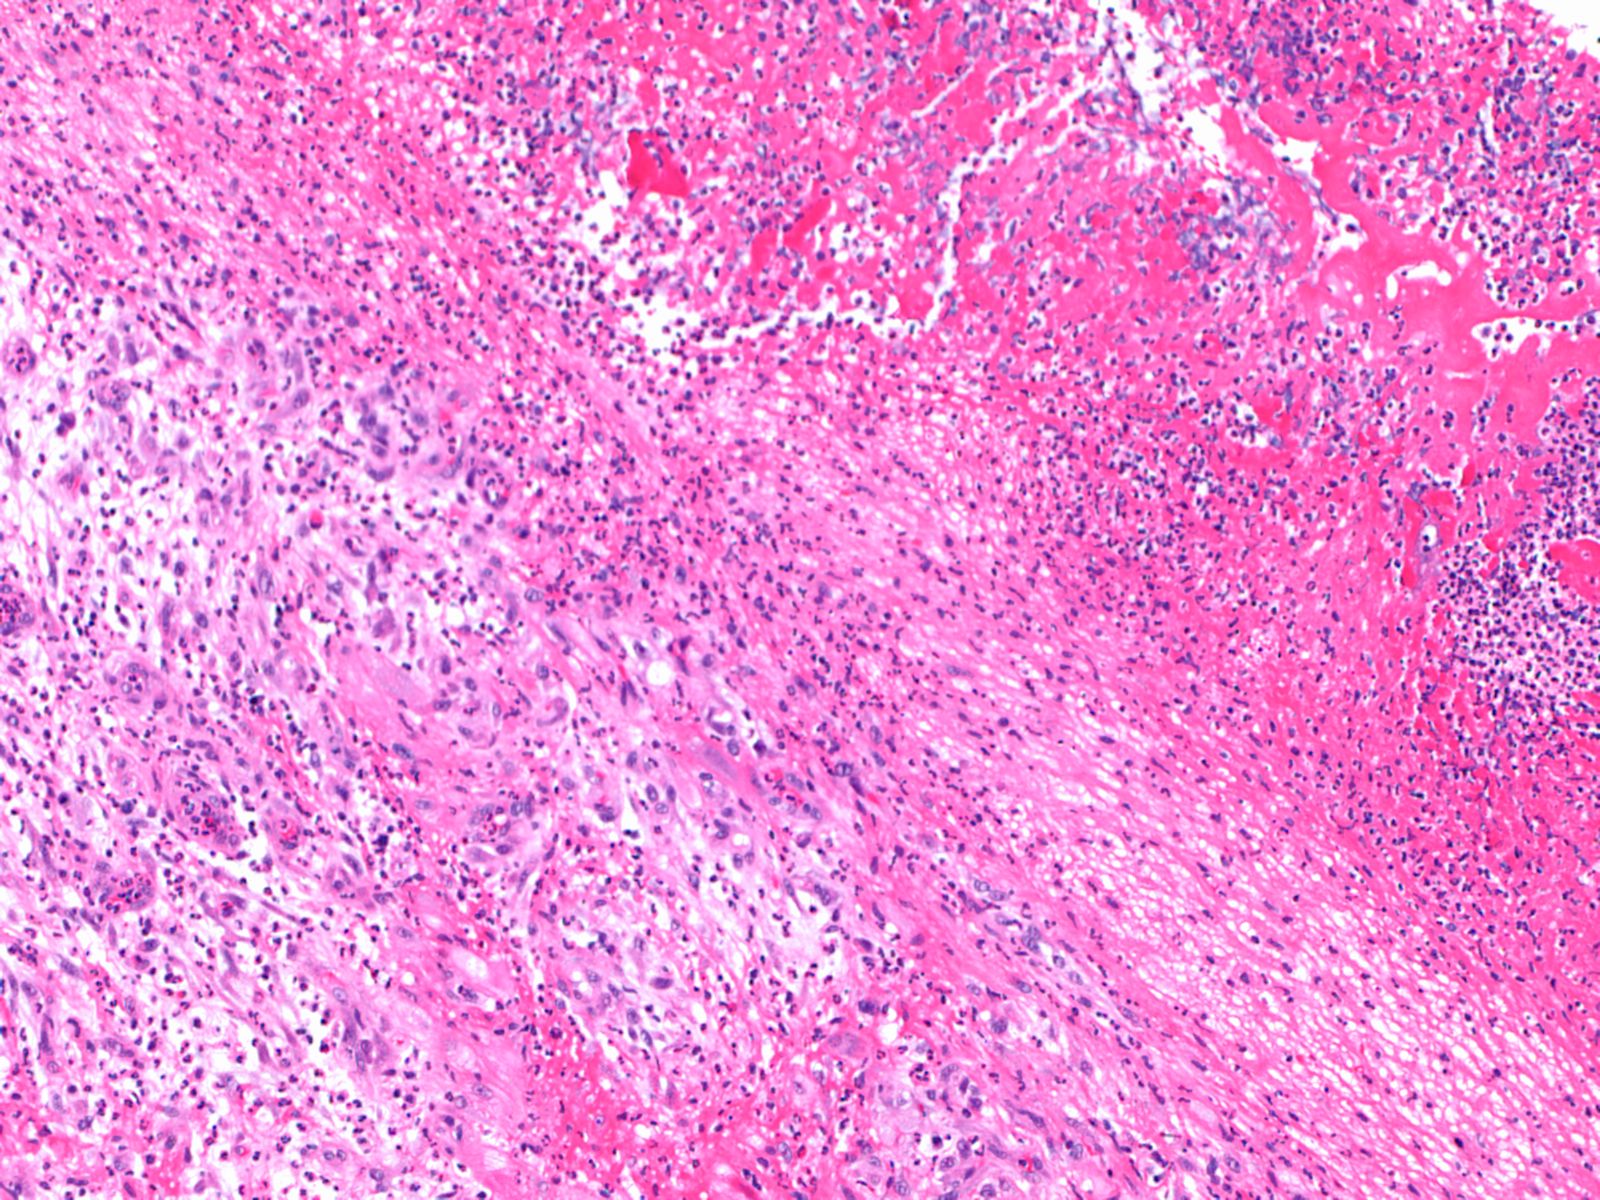

The patient underwent median sternotomy for resection of the vegetation, which was adherent to the papillary muscle, chordae tendinae and posterior wall of the left ventricle, and stained positively for gram positive cocci. (figure 2) Postoperatively, the patient had an uneventful recovery and was discharged home on post-operative day number seven to complete six weeks of intravenous cefotaxime. At the time of follow-up, the patient was found to be doing well with complete resolution of her prior symptoms. Repeat laboratory data, including liver function tests, were entirely within normal limits.